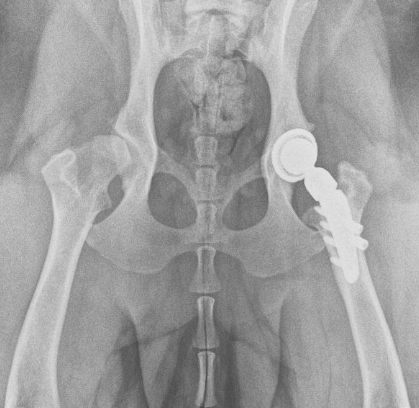

Total hip replacement in Dogs

The other type of hip dysplasia surgery is Total hip replacement (THR). Total hip replacement in dogs involves the removal of the ball and the socket portion of the joint and replacement with a new ball-and-socket, hence “total” hip replacement. Total hip replacement (THR) in dogs is somewhat the opposite of FHO:

- Total hip replacement (THR) in dogs can provide near-normal or normal function. In other words, function and pain relief is superior to what can be achieved with FHO or FHNE

- Canine Total hip replacement (THR) is more expensive than FHO or FHNE.

- Total hip replacement (THR) in dogs has a low complication rate, but some complications can be very problematic and require removal of the implants. Complications of dog total hip replacement can include infection, dislocation, and fracture for example.

- Post-op care for canine Total hip replacement (THR) surgery in dogs requires restriction (ie rest and leashed walking) to try and avoid any of the aforementioned complications

This patient has had a unilateral total hip replacement.